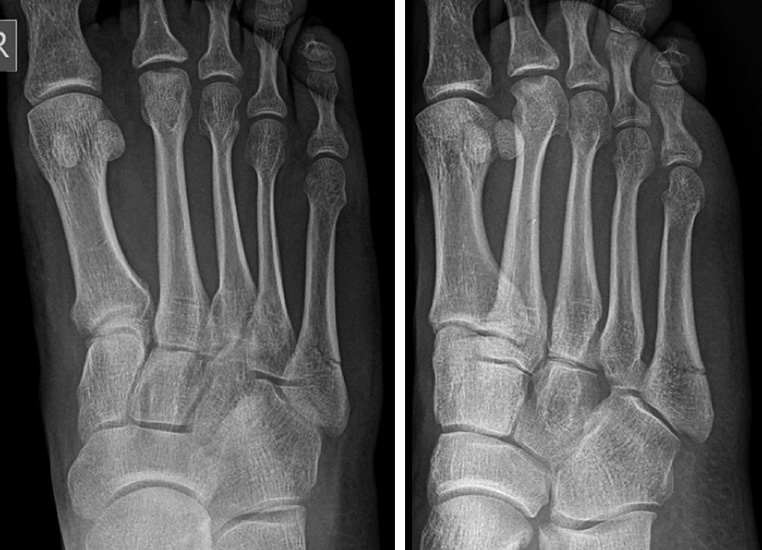

Lawrence und Botte Zone II

Abbildung 4

Kontrovers diskutiert wird die Behandlung der Frakturen in Zone II nach Lawrence und Botte (Abb. 4). Wie einleitend beschrieben, scheint hier unter anderem die inkonsistente Terminologie ursächlich zu sein. Das Synonym „Jones’ Fraktur“ oder „True Jones’ Fraktur“ wurde sowohl für Lawrence und Botte Zone II, als auch für Zone III Frakturen verwendet 1986. Entsprechend ist die Interpretation dieser Studien nur eingeschränkt möglich. 2013 publizierten Roche und Calder 20 eine systematische Literaturarbeit, in welcher sie die Ergebnisse verschiedener Behandlungsstrategien für „Jones Frakturen“ analysierten. 26 Studien mit 630 Frakturen (Level of Evidence I-IV) wurden eingeschlossen. 358 der Frakturen wurden operativ behandelt. Die knöcherne Konsolidierungsrate für operativ versorgte Frakturen betrug 96%, die für konservativ behandelte Frakturen 76%. Allerdings erfolgte keine Differenzierung zwischen Lawrence und Botte Zone II und Zone III Frakturen. Spezifischere Ergebnisse lieferte eine weitere systematische Literaturarbeit 7. In dieser wurden nur prospektive Studien eingeschlossen, in welchen die Frakturen nach Lawrence und Botte klassifiziert wurden bzw. klassifiziert werden konnten. Die Autoren kamen zu dem Ergebnis, dass die frühfunktionelle Behandlung von Lawrence und Botte Zone I und Zone II zu guten bis sehr guten Ergebnissen führt.